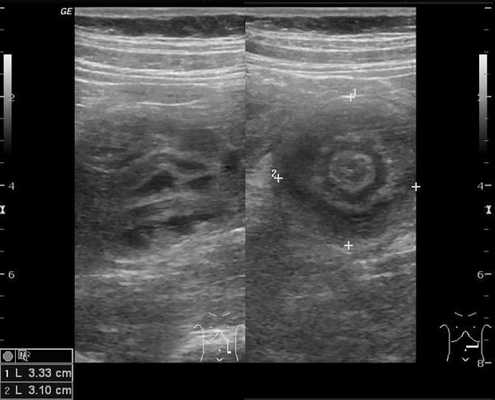

На рисунках 2 и 3 отображена ультразвуковая картина кишечной инвагинации.

Рис. 3. Симптом «псевдопочки»

В момент УЗ-исследования врач может определить один из симптомов:

- симптом "почки с завоздушенным центром".